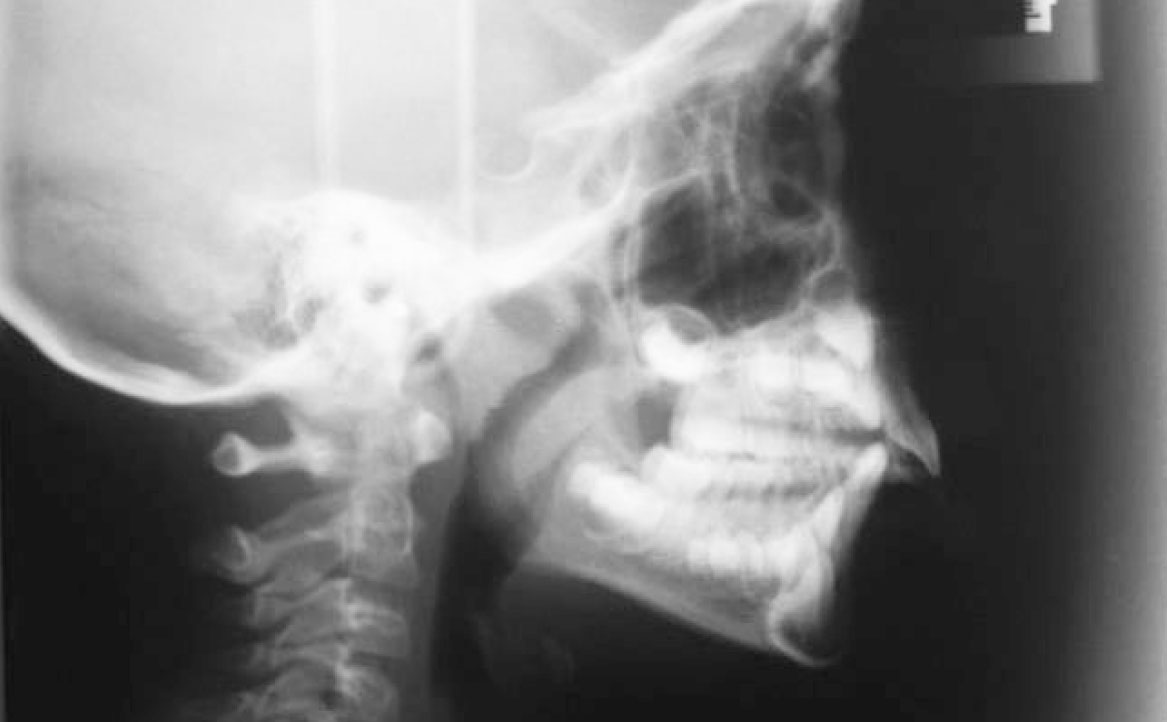

Sono state eseguite fotografie extra- e intra-orali ed esami radiografici (OPT e teleradiografia latero-laterale), che hanno evidenziato una relazione scheletrica di Classe II da retrusione mandibolare.

Viene eseguita la consueta raccolta dei records: fotografie intra ed extra orali, modelli e indagini radiografiche di primo livello (OPT e teleradiografia latero-laterale) (fig. 2-11).

L’esame clinico e strumentale consentono di porre diagnosi di malocclusione di classe II di natura scheletrica, associata a retrusione mandibolare. In questa condizione, la mandibola mostra dimensioni e volume inferiori rispetto ai valori medi per età scheletrica e sesso.

Extraoral and intraoral photographs were taken, along with radiographic exams (panoramic radiograph and lateral cephalometric radiograph). The diagnosis confirmed a skeletal Class II relationship due to mandibular retrusion.